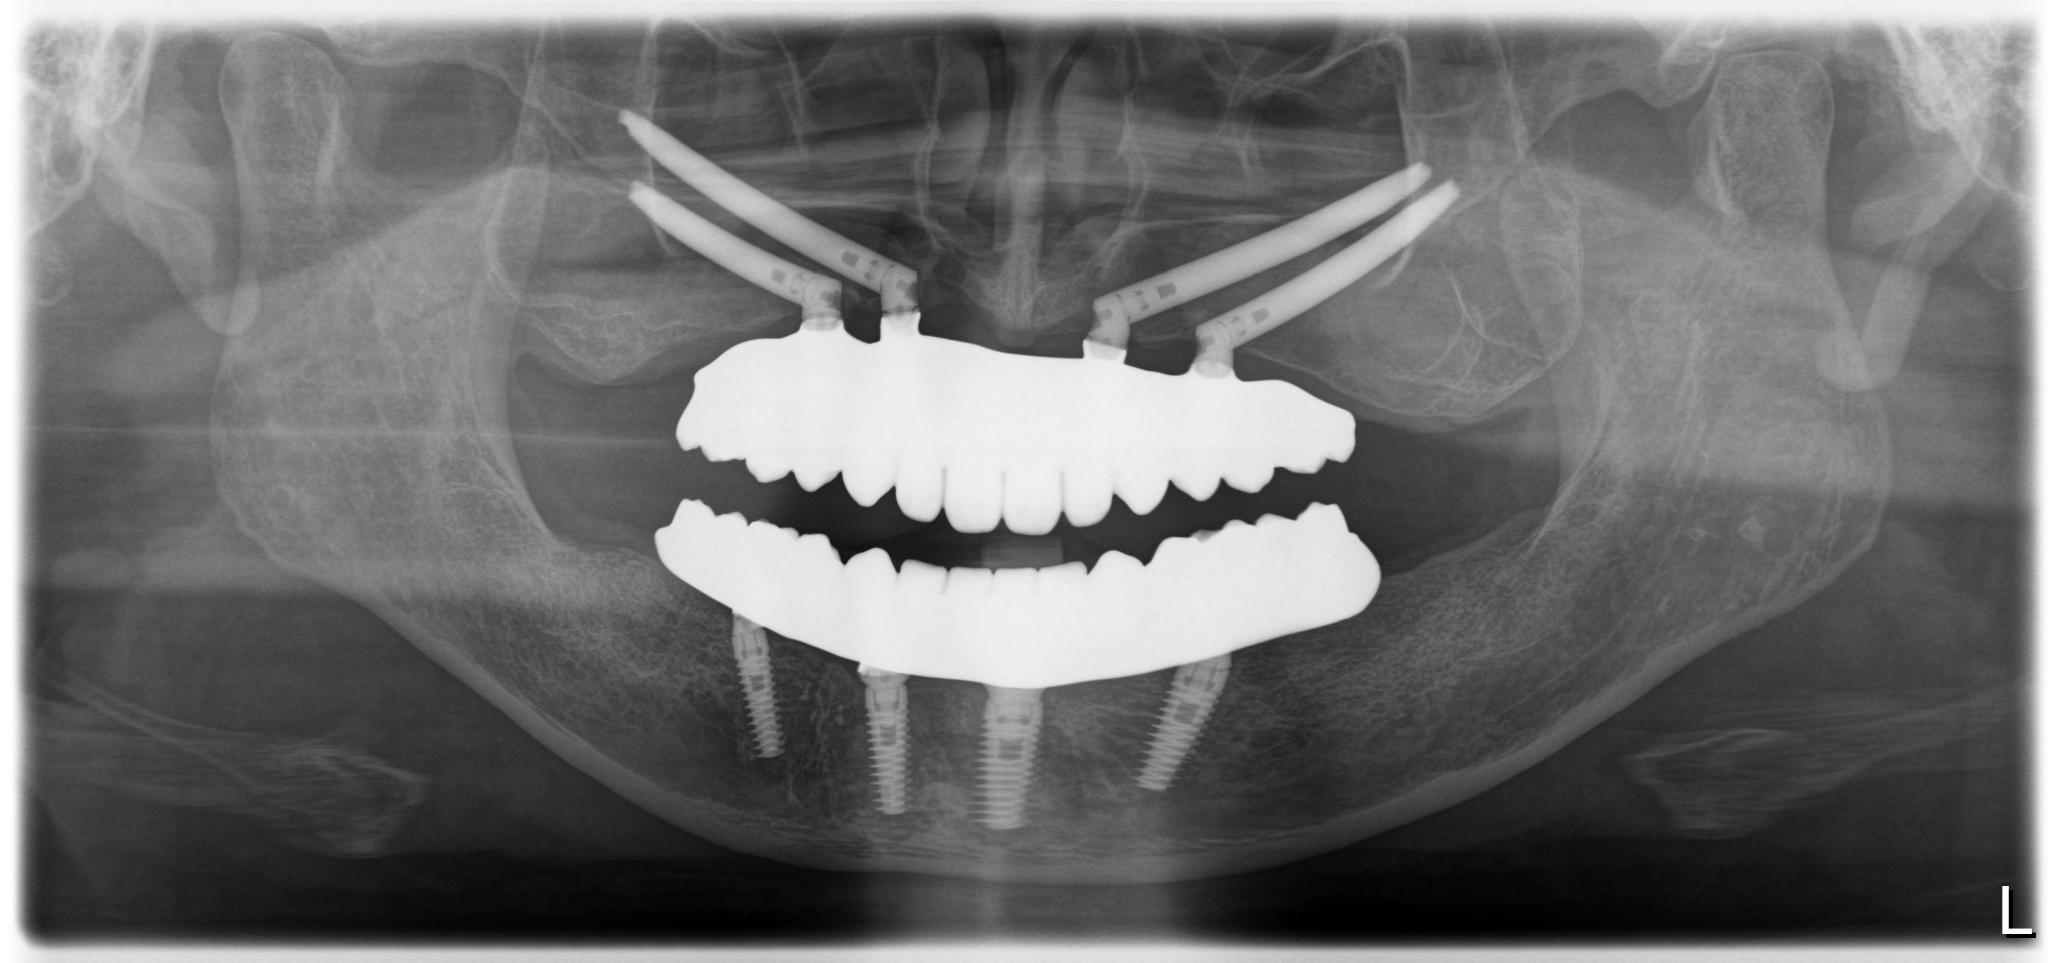

術後

内容 :上下顎オールオン4ザイゴマ4

費用 :5,500,000円

※モニター価格

期間 :半年

リスク:出血・腫れ・痺れ・痛み